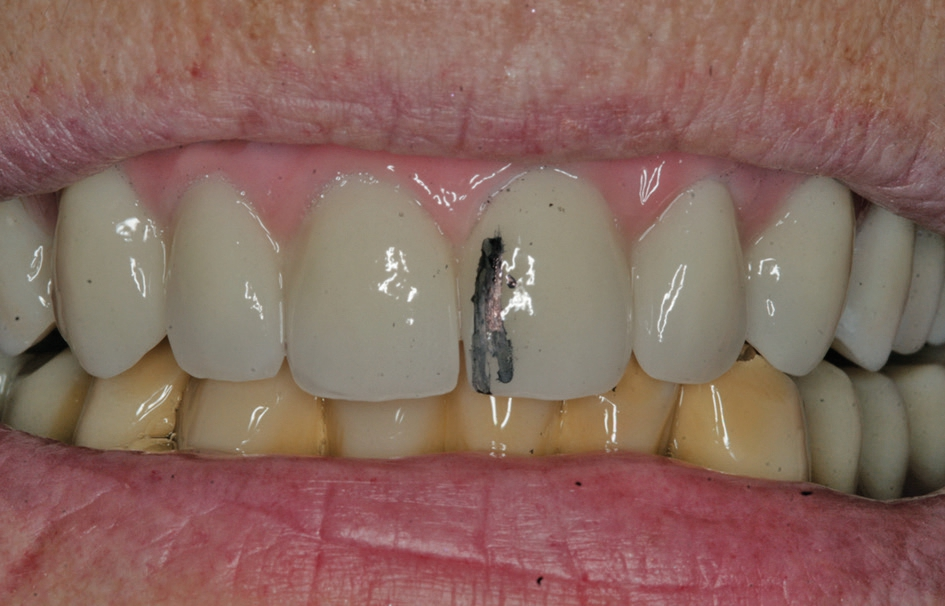

Nach einer initialen Abformung können vom Zahntechniker die optimalen Aufbauten nach der physiologischen Aufstellung und Wachseinprobe ausgewählt werden (Abb. 7 bis 9). Diese werden dann in die Implantate eingeschraubt und verbleiben dort, ohne dass sie wieder entnommen werden. Durch die Auswahl der Aufbauten vom Zahntechniker kann dort auch gleich eine Verblockung vorbereitet werden, mit der es möglich ist, die endgültig erreichte Position der angulierten Aufbauten direkt in das Labor zu übertragen. Somit stellt das Meistermodell eine identische Kopie der klinischen Situation dar. Dies ist notwendig, damit im Rahmen von CAD/CAM-Verfahren Gerüste für die weitere prothetische Versorgung gefräst werden [14]. Je nach Umsetzung der patientenindividuellen Aufstellung kann die definitive Versorgung hergestellt werden. Dort bestehen heute die Möglichkeiten der CAD/CAM-Technologien mit einem Titan- oder einem Keramikgerüst zur Verfügung. Sofern sich kein absolut passgenaues Gerüst erreichen lässt, kann dies durch eine Klebebasis kompensiert werden [5]. Dies wird in der Regel bei reinen Zirkonoxidgerüsten erforderlich. Im weiteren Ablauf kann die individuelle Charakterisierung der Vestibulärflächen und des Weichgewebsübergang erreicht werden (Abb. 10 bis 14).